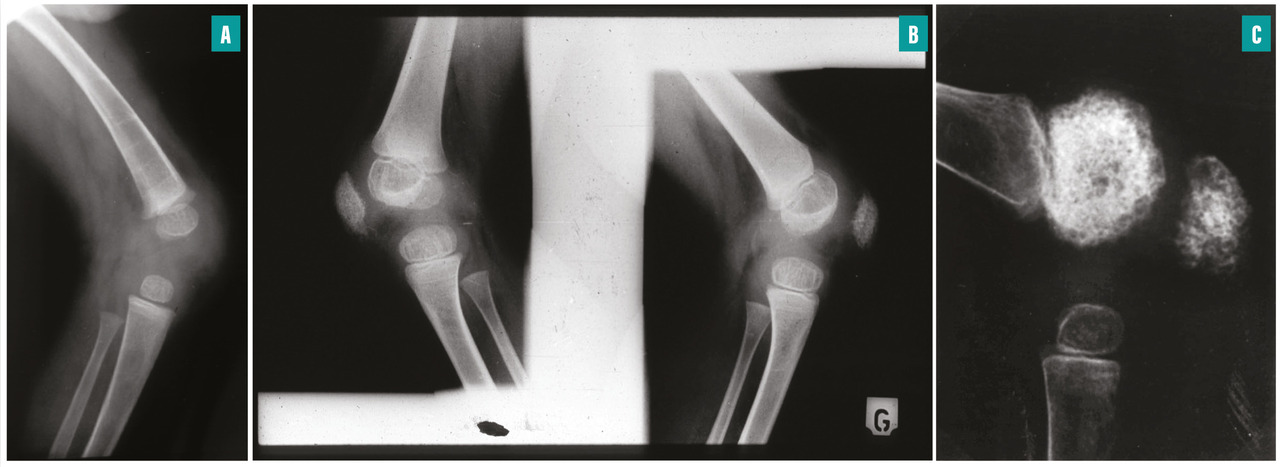

Radiographie osseuse du genou chez un enfant atteint de CINCA souffrant d’une arthropathie hypertrophiante précoce : respectivement à 6 mois (A), 2 ans (B) et 3,5 ans (C). On observe une irrégularité des métaphyses et épiphyses, une hypertrophie irrégulière progressive avec un aspect « en mie de pain » des épiphyses et de la rotule.